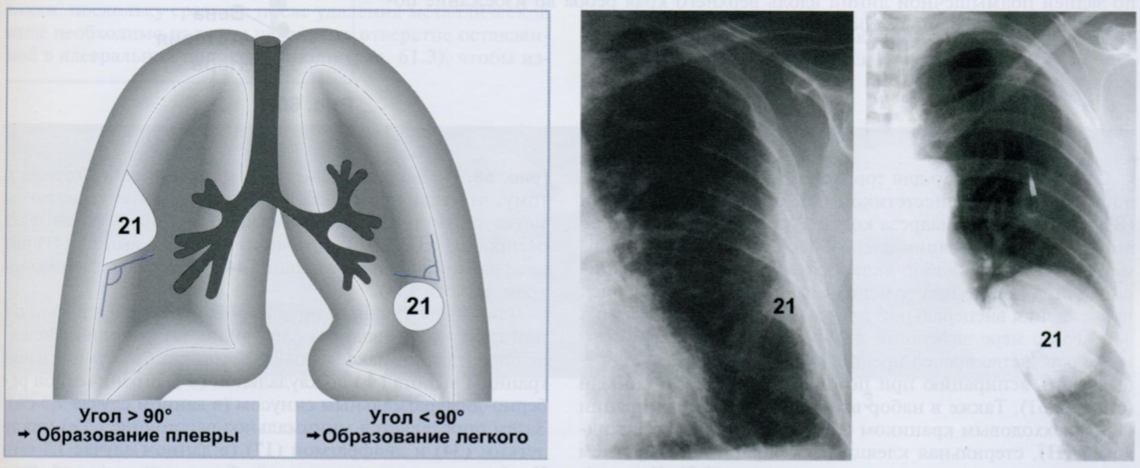

Правило Ленка (схема) помогает установить, исходит ли внутригрудное образование (21) из плевры или легочной ткани.

Образования плевры на боковой стенке грудной клетки, видимые в профиль, образуют с грудной стенкой тупой угол (> 90°) (первая Rx). Это отличает их от внутрилегочных образований, расположенных рядом с плеврой, которые образуют с грудной стенкой острый угол (< 90°) (вторая Rx).